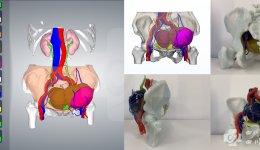

• 胃肠外科与医学3D打印中心医工结合实施肿瘤精准切除

胃肠外科与医学3D打印中心医工结合实施肿瘤精准切除

近日,我院胃肠外科副主任医师周晓刚、主治医师覃先蓬团队和好上课创伤修复中心副主任医师李峥团队联合医学3D打印中心,首次应用3D打印技术完成腹腔腹壁多发复发病变的术前规划,通过医工结合成功应用3D打印模型技术和可视化技术完成腹腔腹壁多发复...